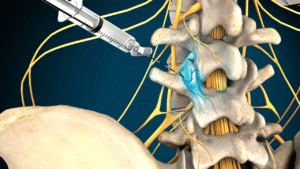

- Minimal-invasive Eingriffe

Rückenschmerzen

Schmerzen im unteren Rücken sind eine sehr häufige Erkrankung. Sie können verschiedene Ursachen haben, z. B. Muskel-, Gelenk- oder Bandscheibenprobleme, und schränken oft die täglichen Aktivitäten ein.